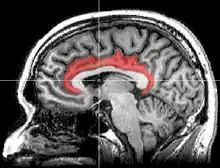

![]() Medial surface of left cerebral hemisphere, with cingulate gyrus and cingulate sulcus highlighted. | |

The cingulate cortex is a part of the brain situated in the medial aspect of the cerebral cortex. The cingulate cortex includes the entire cingulate gyrus, which lies immediately above the corpus callosum, and the continuation of this in the cingulate sulcus. The cingulate cortex is usually considered part of the limbic lobe.